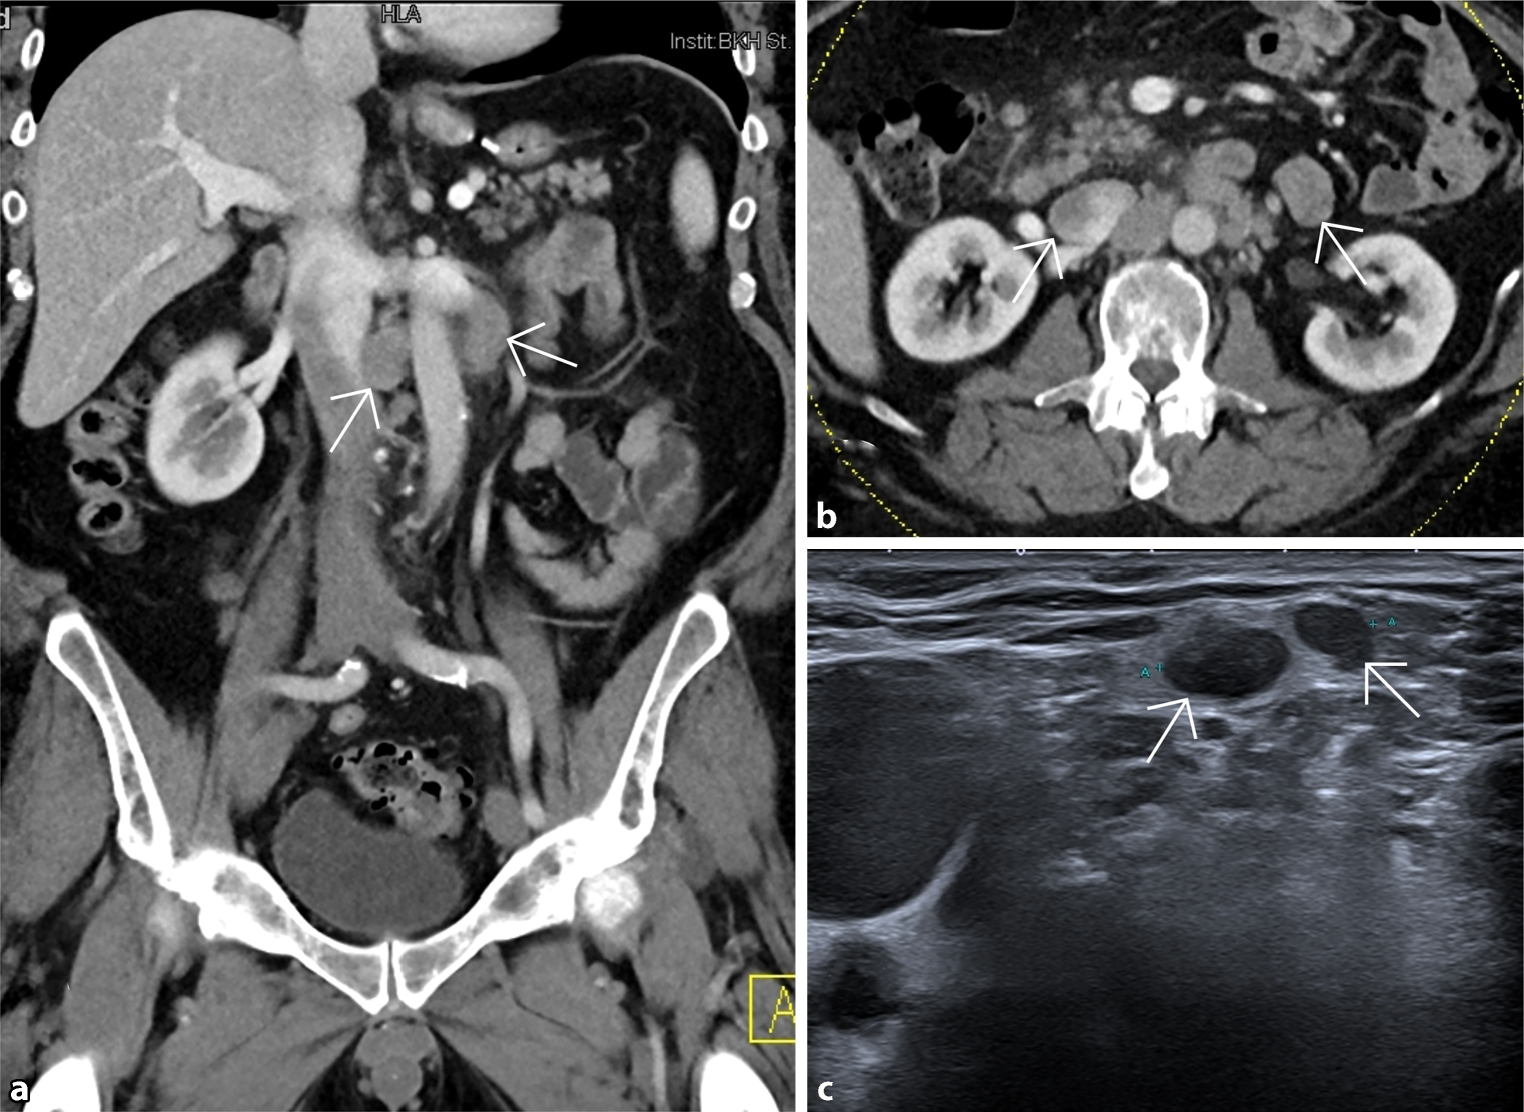

Diagnostic workup included upper gastrointestinal (GI) endoscopy, which was unremarkable except for mild reflux esophagitis and colonoscopy, showing hemorrhoids grade 3 as potential cause of the bleeding. Due to persistent abdominal pain, we conducted an abdominal computed tomography (CT) scan with oral and intravenous contrast, which revealed para-aortic and mesenterial lymphadenopathy (Fig. 1). A thoracic CT scan demonstrated mediastinal lymphadenopathy. An endobronchial ultrasound-guided needle biopsy of paratracheal lymph nodes showed no evidence of malignancy. With persisting symptoms and extensive lymphadenopathy, we conducted an 18F-FDG PET-CT scan, detecting several cervical tracer-enriched lymph nodes and suspect lymph node stations in the mediastinum and abdomen. One suspicious, wire-marked supraclavicular lymph node was removed. Histological analysis demonstrated a poorly differentiated adenocarcinoma of gastrointestinal origin with HER2 positivity on FISH testing. Serum levels of CEA (18.3; normal 0–3 ng/mL) and CA72‑4 (11.1; normal 0–6.9 U/mL) were above the normal range. Although previous endoscopy showed normal findings, the histology strongly suggested a malignancy of gastrointestinal origin. Together with the department of nuclear medicine, we re-examined the diagnostic imaging, detecting slight tracer enrichment at the site of the gastric remnant. These results prompted an explorative laparoscopy to confirm the diagnosis. Wedge resection of the anterior wall of the gastric antrum was performed (Fig. 2). No peritoneal carcinosis or dissemination to other organs was detected. Subsequent histology taken from the gastric remnant confirmed the diagnosis of HER2-positive gastric cancer on immunohistochemistry testing (HER2 3+) with distant lymph node metastasis (intestinal type Lauren pT3, NX, L1, V1, R0, M1; UICC IV).

Fig. 1

a CT scan (frontal)—enlarged para-aortic lymph nodes, b CT scan (axial)—enlarged para-aortic lymph nodes, c ultrasound: 17 mm large wire-marked supraclavicular lymph node